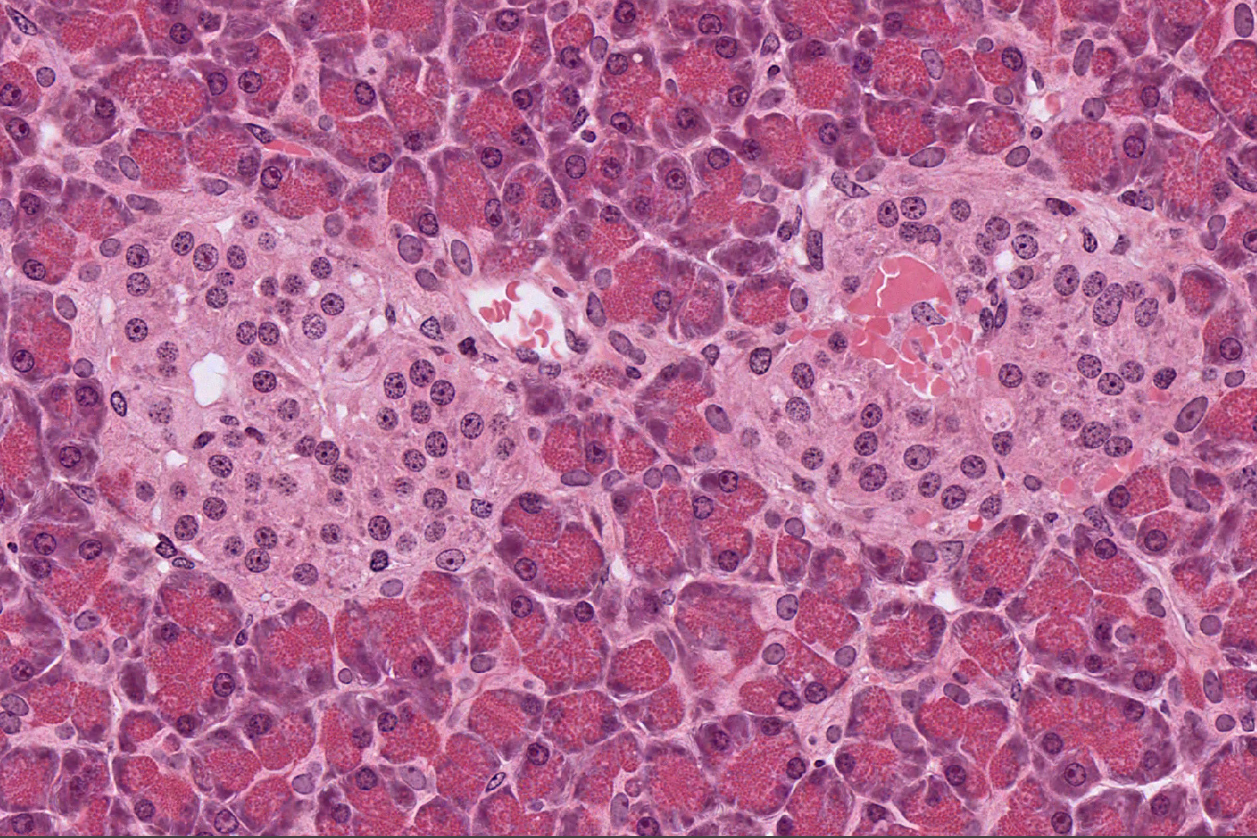

Pancreas

NOTICE: ISLET OF LANGERHANS WHICH ARE ENDOCRINE CELLS ALL PACKED TOGETHER

NOTICE: ISLET OF LANGERHANS WHICH ARE WHERE ENDOCRINE CELLS ALL PACKED TOGETHER

Pacreas